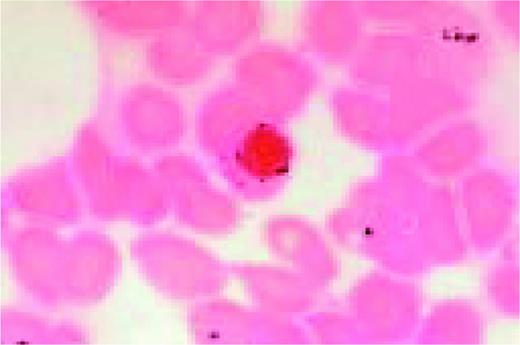

Slide MG5

Bernard-Soulier syndrome. High-oil magnification view of a patient with the Bernard-Soulier syndrome. A typical giant platelet is seen in the center of the field.FIG87